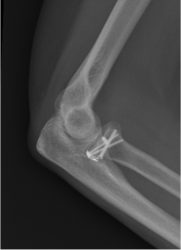

1b. X-rays after surgery, showing the fracture after fixation

A rotation of the x-ray